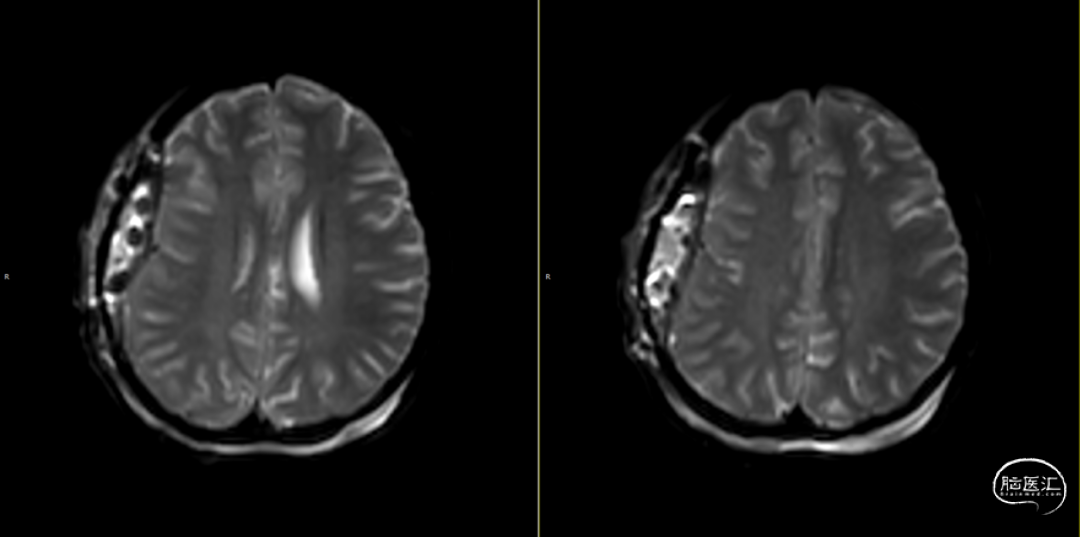

2024-07-21 08:58:55术后58天复查(如上图)。

术后58天颅脑磁共振平扫(如上图):右侧额顶颞部见斑片状异常信号,呈片状T1WI低、T2WI稍高信号影,T2FLAIR呈稍高信号,边界清,右侧额顶颞叶脑组织受压,DWI(b=1000)呈混杂高信号,相应ADC呈混杂高信号影。